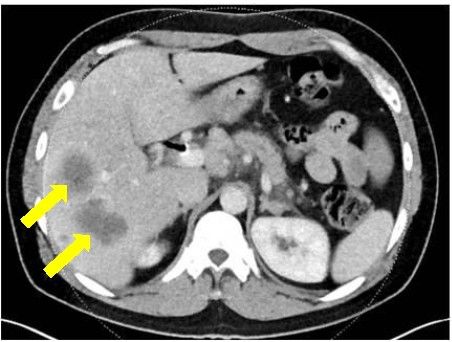

确诊时

令人感到惊讶的是,他的胰腺和肝脏恶性肿瘤开始迅速缩小,随后几个肿瘤几乎完全消失。 要知道,对这种化疗方案完全响应的患者非常少。他们被称为“特殊应答者”。

FOLFIRINOX治疗5个月病灶明显缩小 vs olaparib治疗21个月病灶全部消失